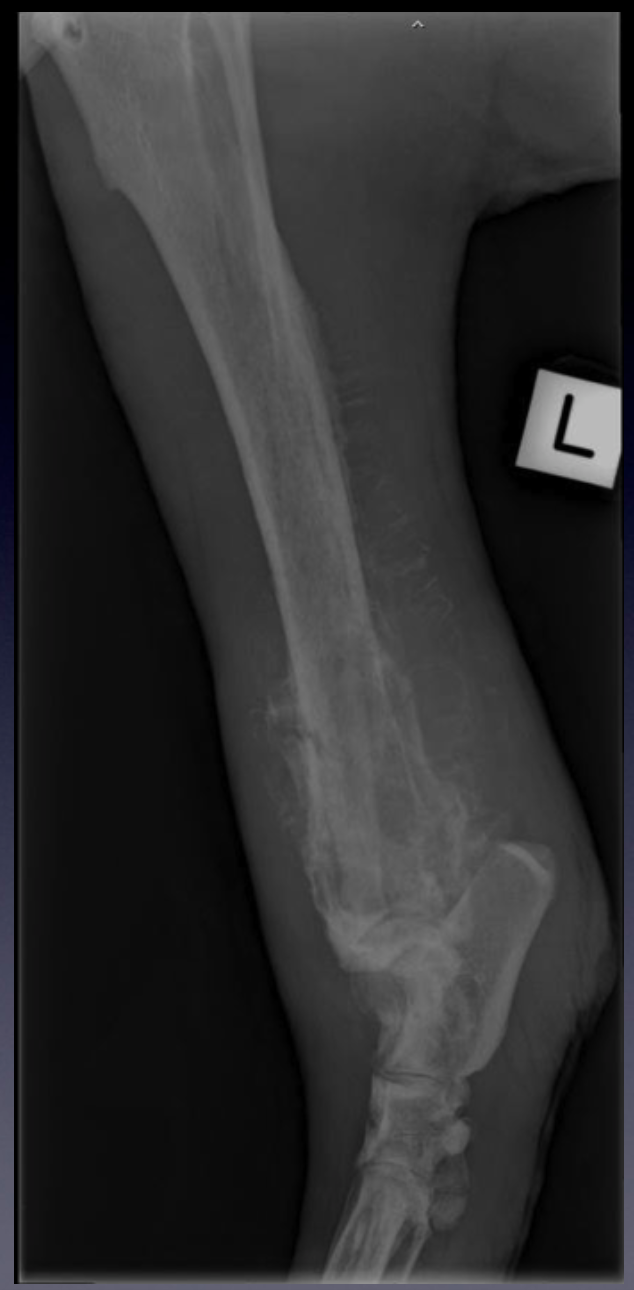

Case 3: Patient 231270

VIEW?

Marked soft tissue swelling around the distal aspect of the crus

The aggressive bone lesion in the distal tibia.

The pathologic fracture in the distal tibial diaphysis - note the lucent lines through the cranial and

caudal cortex

Mediolateral projection of the tarsus